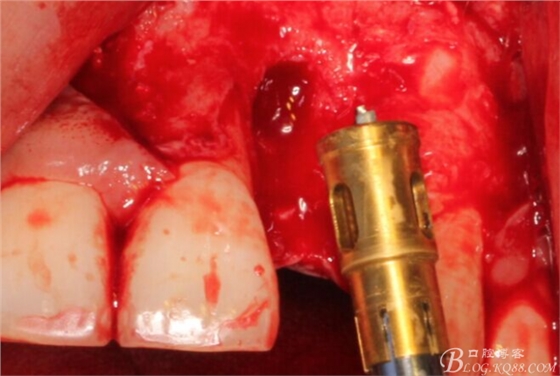

根方用取骨鉆取自體骨。